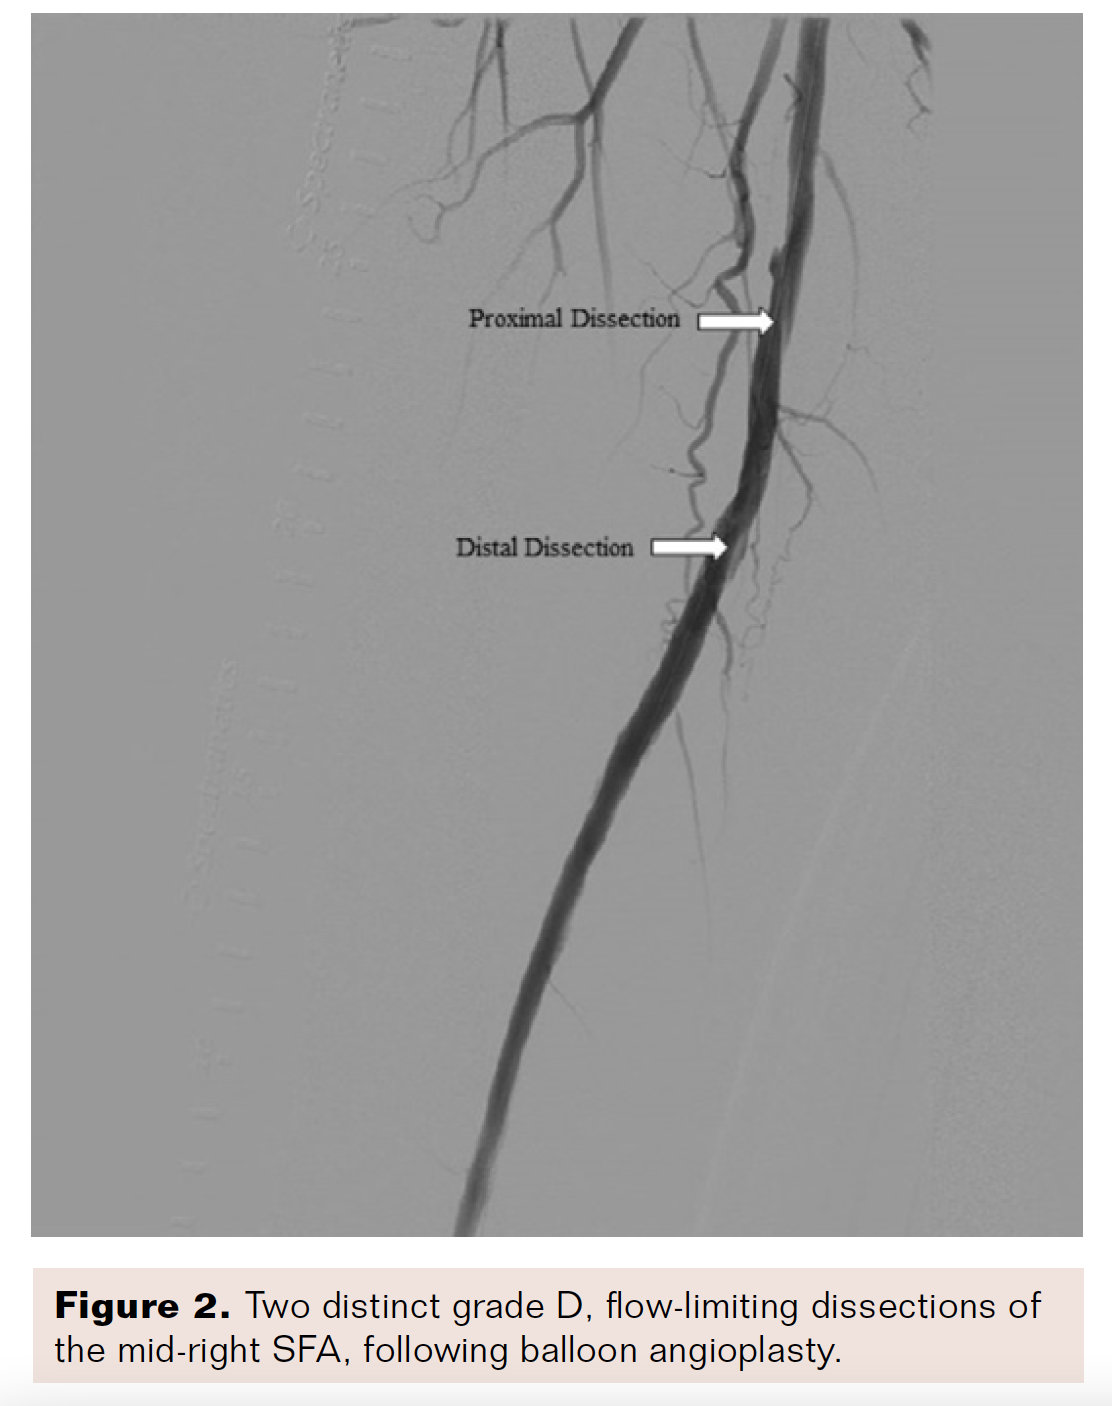

During the index procedure for the right lower extremity, an OmniFlush catheter (AngioDynamics) was positioned at the level of the right common femoral artery (CFA) for selective angiography with runoff (Figure 1). A Runthrough NS Extra Floppy guidewire (Terumo) was used to traverse the diseased segment. The Runthrough guidewire was exchanged for an .018-inch NiT-Vu guidewire (AngioDynamics) through a Glidecath support catheter (Terumo), and the lesion was prepared with a 5 × 80 mm Armada PTA balloon (Abbott Vascular). After vessel preparation, another balloon angioplasty was performed with a 6 × 120 mm Lutonix drug-coated balloon PTA catheter (BD). Angiography demonstrated less than 10% residual stenosis, but there were two grade D, flow-limiting dissections that were located in the mid-right SFA (Figure 2), disrupting an optimal hemodynamic result.